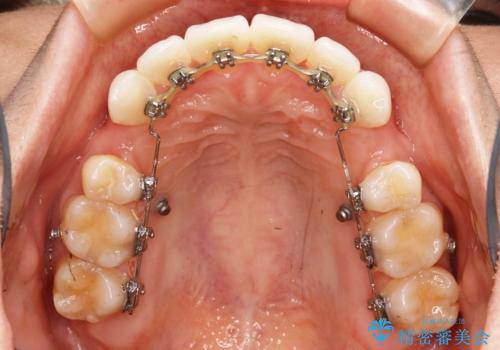

- ワイヤー(片顎舌側装置)

- 歯のガタつきと出っ歯感を治したいとの主訴でご来院され、ハーフリンガル装置を希望なさったため、検査を行ったうえで上下左右4番目の歯を抜歯し歯列を内側に引っ込めつつ叢生の改善を行うこととなりました。

ハーフリンガル装置

ハーフリンガルとは上顎を裏側、下顎を表側のワイヤー装置で治療する場合をいいます。